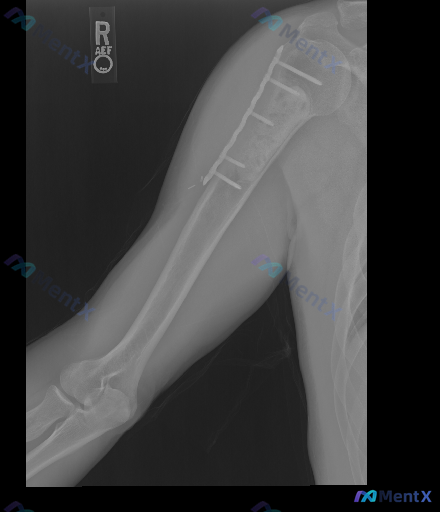

整理到一张右侧上臂(肱骨)正位X光片的影像资料,先不说结论,只看描述大家第一眼怎么考虑? 核心影像表现(精简整理): - 右肱骨近端有金属接骨板+螺钉固定,位置总体在位,未见明显断钉/松动脱出 - 接骨板下方肱骨干近段:骨皮质不连续,可见清晰骨折线,断端之间有明显间隙,还有轻度骨吸收 - 肩关节、肘...